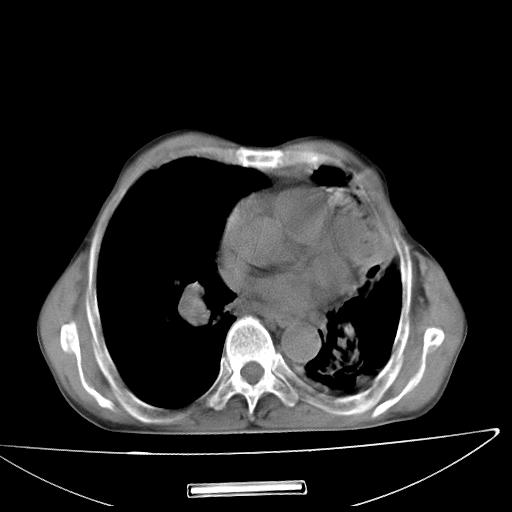

男  70岁,发烧咳嗽4天。盗汗,消瘦。无痰中带血丝,以前有肺tb病史,ct见,双肺tb,左侧胸廓塌陷,左胸膜肥厚粘连。纵隔移位,右侧胸腔积液,大家说说那个心影前左肺舌叶除了肺大炮还有炎症还是干酪性肺炎?有占位吗?我看纵隔淋巴结也大。

1)两肺继发性肺结核并左肺上叶肺不张,支气管扩张。2)双侧胸膜炎(胸膜增厚+少量胸腔积液)。

两肺继发性肺结核并感染,左肺上叶肺不张。建议ct增强。